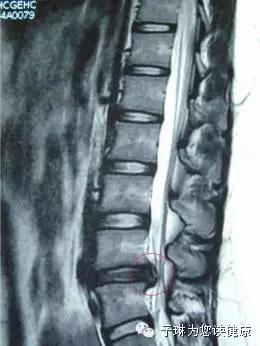

图:徐鹏的腰椎间盘核磁共振检查

经过CT和核磁检查,孙凤龙医生在徐鹏的腰椎间盘上发现了明显的突出物(如上图红色圈住的部分),再结合他的症状,到底是什么疾病此时已经非常明显,和孙凤龙教授门诊上60%的患者遭遇的是同一个问题——腰椎间盘突出症。只是他的病情已经非常严重了。